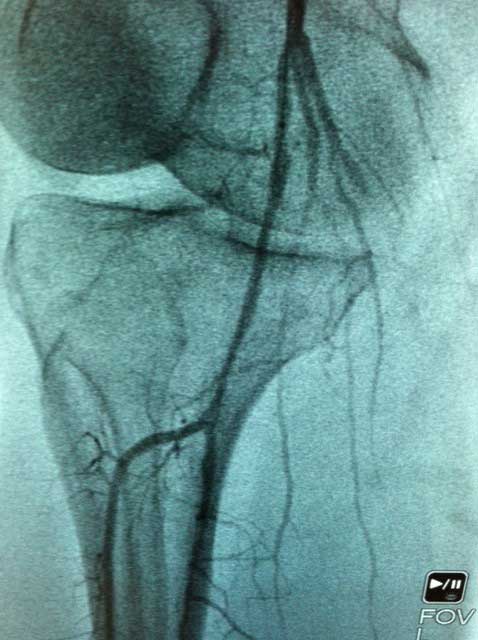

Interventional case 3